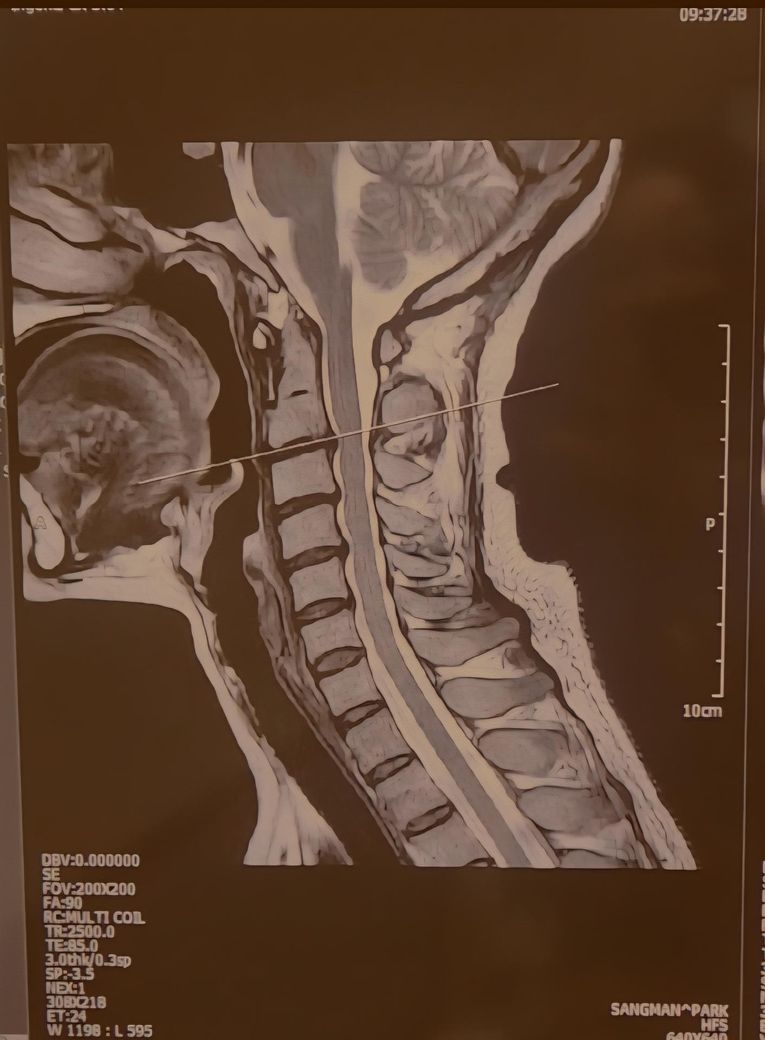

목디스크 판정받았는데..연관통 증상 문의드려요

얼마전 2.3.4.5번 경추디스크 판정받았는데요

• 1번 째 사진